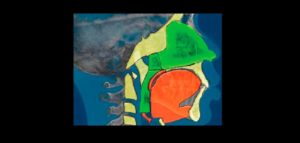

132 – Tratamiento de la reabsorción radicular interna idiopática perforante: controles radiográficos

La reabsorción radicular interna (RRI) es una afección inflamatoria que resulta en la destrucción progresiva de la dentina intra-radicular a lo largo de los tercios